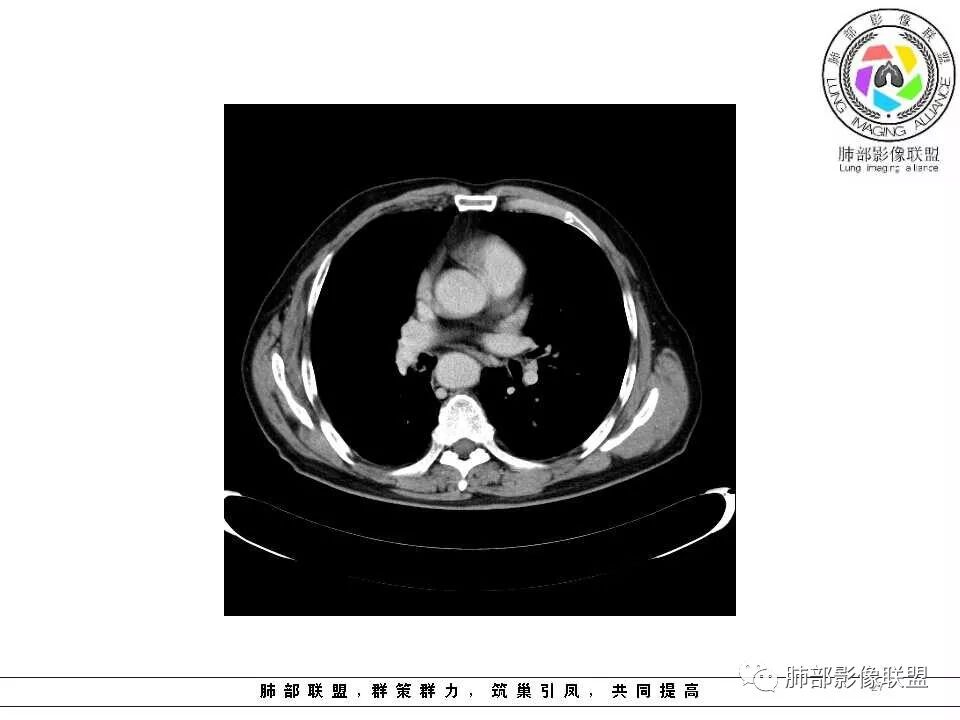

影像学特点:肺气肿背景下在大概一年的时间里出现了一个光滑的小结节,因为图像给的不是太薄,与支气管的关系判断不清,从结节周围出现斑片状炎症来判断,应该考虑结节位于支气管内,周围是阻塞性炎症,这样比较容易解释咯血

纵隔窗上似乎结节内可见点状高密度影,同时没有明显肿大淋巴结

老年男性,肺气肿背景,左肺上叶舌段病灶明显增大,变异膨隆,远端阻塞肺炎,考虑鳞癌。

左肺上叶小结节病灶,形态规则,边缘光滑,密度至密,远处阻塞性肺炎,病灶与支气管关系密切,给图太少不好观察,考虑神经内分泌癌(类癌),其次鳞癌

老年男性,有咳血病史,左肺上叶舌段一年时间出现新发类圆形小结节,感觉在支气管内,部分凸出气管外,没有mpr不好说,远端肺野斑片模糊影,考虑阻塞性炎症,纵隔无明显肿大淋巴结,小细胞代排,按照发展速度,类癌低度恶性,应该发展缓慢,一年病史,代排,首先考虑鳞癌并阻塞性炎症

左肺上叶舌段支气管管壁略增厚 间隔一年 管壁增厚明显 向腔外突出形成结节 管腔闭塞 远端片状及斑片影 纵隔淋巴结增大 肺气肿背景 考虑鳞癌伴阻塞性炎症可能

老年男性,咯血1月,肺气肿背景,16年左肺上叶舌段结节,左肺门疑似淋巴结肿大,呈结节感。17年左肺上叶舌段见沿支气管走行分布结节 远端阻塞性肺炎,左肺门淋巴结肿大明显,首先考虑恶性病变,鳞癌?类癌?

老年男性,肺气肿背景,左肺上叶舌段一年前小结节后长大,实性,与邻近气管关系密切,远端有少许小片状炎症类小结节状,左肺门淋巴结肿大,首先考虑恶性,鳞癌可能性大,代排小细胞癌。病灶下方斑片状影,考虑炎症。

老年男性,咯血1月,肺气肿背景,左肺上叶舌段见沿支气管走行分布结节,呈葫芦样改变,左肺门淋巴结肿大明显,首先考虑恶性病变,小细胞癌可能